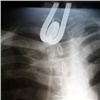

Красноярские врачи спасли проглотившего кипятильник парня Красноярские врачи спасли проглотившего кипятильник парня 116

Он утверждал, что проглотил кипятильник «случайно».